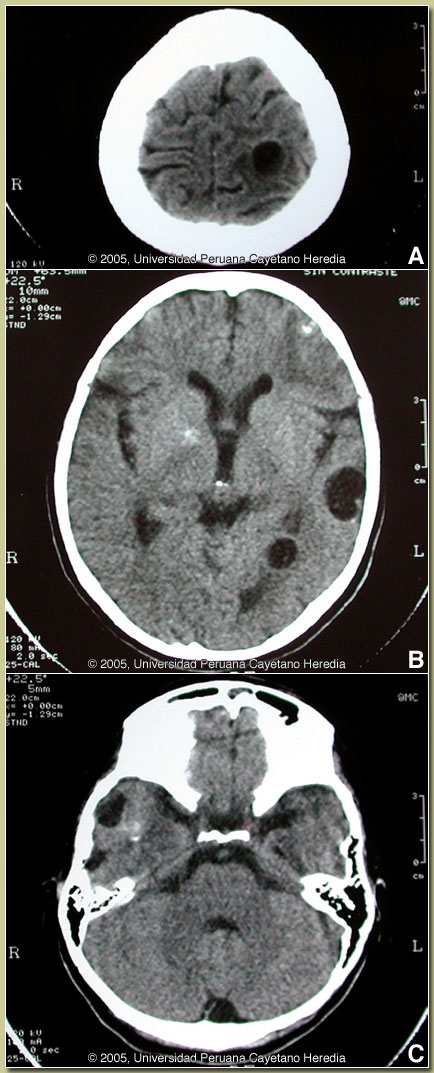

| Diagnosis: Neurocysticercosis. Unrelated parathyroid adenoma. |

| Discussion: A western blot was positive for T. solium. The CT scan showed multiple viable lesions of cysticercosis (some with the scolex inside) plus some calcifications. No intracranial hypertension is obvious. A thyroid scan revealed a parathyroid nodule, which on biopsy was an adenoma and not a cysticercus.